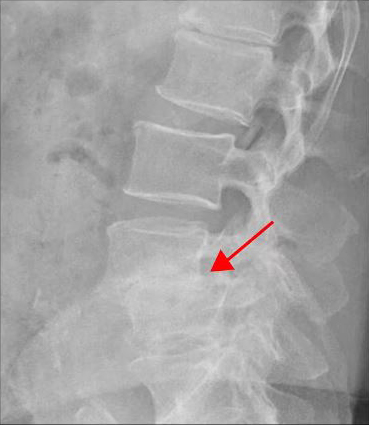

<4-5번 척추전방전위증>

이 환자분은 요추 4-5번 오른쪽에 심한 추간공협착증, 2단계의 전방전위증이 있으며, 특히 전방전위증으로 인해 추간공이 매우 좁아져 있습니다. 또 요추 5-1번 왼쪽에 디스크 파열이 있습니다.